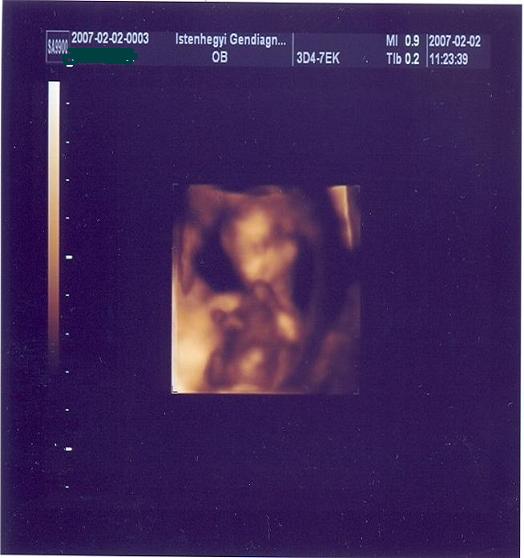

Na, a csütörtöki napomnál kezdem. Szóval, voltam a nődokinál, de annyira szorakozott volt, és kapkodott, kicsit bosszús voltam rá :( . Párom aztán hívta a nőgyógyász barátját, és azt mondta, hogy ez a baba nagy ahhoz, hogy még csak 10hetes legyek, menjünk fel másnap az istenhegyi klinikára, mert látni akar :( . Persze keveregtek bennem a gondolatok, hogy biztos valami baj van, és mi van ha elkerültem a 12.hetet, és arról a vizsgálatról meg lemaradtam :( .. Szóval mindenre tudtam gondolni csak jóra nem :( . Ott megcsinálták a kombinált tesztet, minden rendben van, kaptunk szép fotókat, és egy 15perces dvd-t :) . Nem volt szégyenlős a drágám, forgolódott, járt keze-lába. Nekem még a könnyeim is kipotyogtak, a párom is nagyon elképedt, nem bírt betelni vele :) . Szóval kiderült, hogy 13hét+2napos vagyok. Ugye megint ideges lettem, mert egy kicsit megrendült a bizalmam a dokim felé, és hazafelé eldöntöttük, hogy ide az ismerőshöz fogunk járni, már szóltunk is neki, és nagyon szívesen átvesz :) .

szerintetek is olyan, mintha mosolyogna :?:

Nagyon szép mosolygós babád van, Mona! :)

12 hetesen/illetve13 :)/ ilyen jó kis képet kaptál :D én is gondolkodom a 4 D-n még 18 hét előtt ,mert kiváncsi vagyok nagyon.

És ha jobban megnézzük a képet tényleg olyan, mintha a szája nevetésre állna :wink: kis keze a szája szélénél van épp a mosoly szélén.Nagyon édi bébi :wink:

A mi babónkról még csak ez a kép van ,de azért látszik a drága.